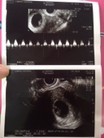

ซาวด์ครั้งแรกท้อง11วีคก้เจอแบบนี้เรยค่ะเสียใจกังวลมากค่ะอีก2อาทิตย์หมอนัดอีกเรายังมีหวังที่จะเจอตัวน้องยุไหมคะสอบถามแม่ๆที่เจอเรื่องแบบนี้หน่อยค่ะขอบคุณสำหรับคำตอบค่ะ😔

อย่ากังวลน่ะค่ะแม่ๆๆ.. บ้านนี้เจอน้องตอน13วีคแล้วค่ะ... สู้ๆ

เราซาวตอน8wไม่เจอ มาเจอตอน12wใจเย้นๆนะน้องยังตัวเล็กยุ่

อย่าพึ่งกังวลนะคะ บ้านนี้ซาวเจอหัวใจน้องตอน13วีคเลย

รอสัก 12-13 weeks ค่อยดูอีกทีดีกว่านะคะ เป็นกำลังใจให้ค่ะ

มีโอกาสที่จะเป็นท้องลมสูงมากค่ะ...สู้ๆนะคะ

บ้านนี้เจอน้องตอน 8w2d คะ รอซาวน์อีกรอบนะคะ